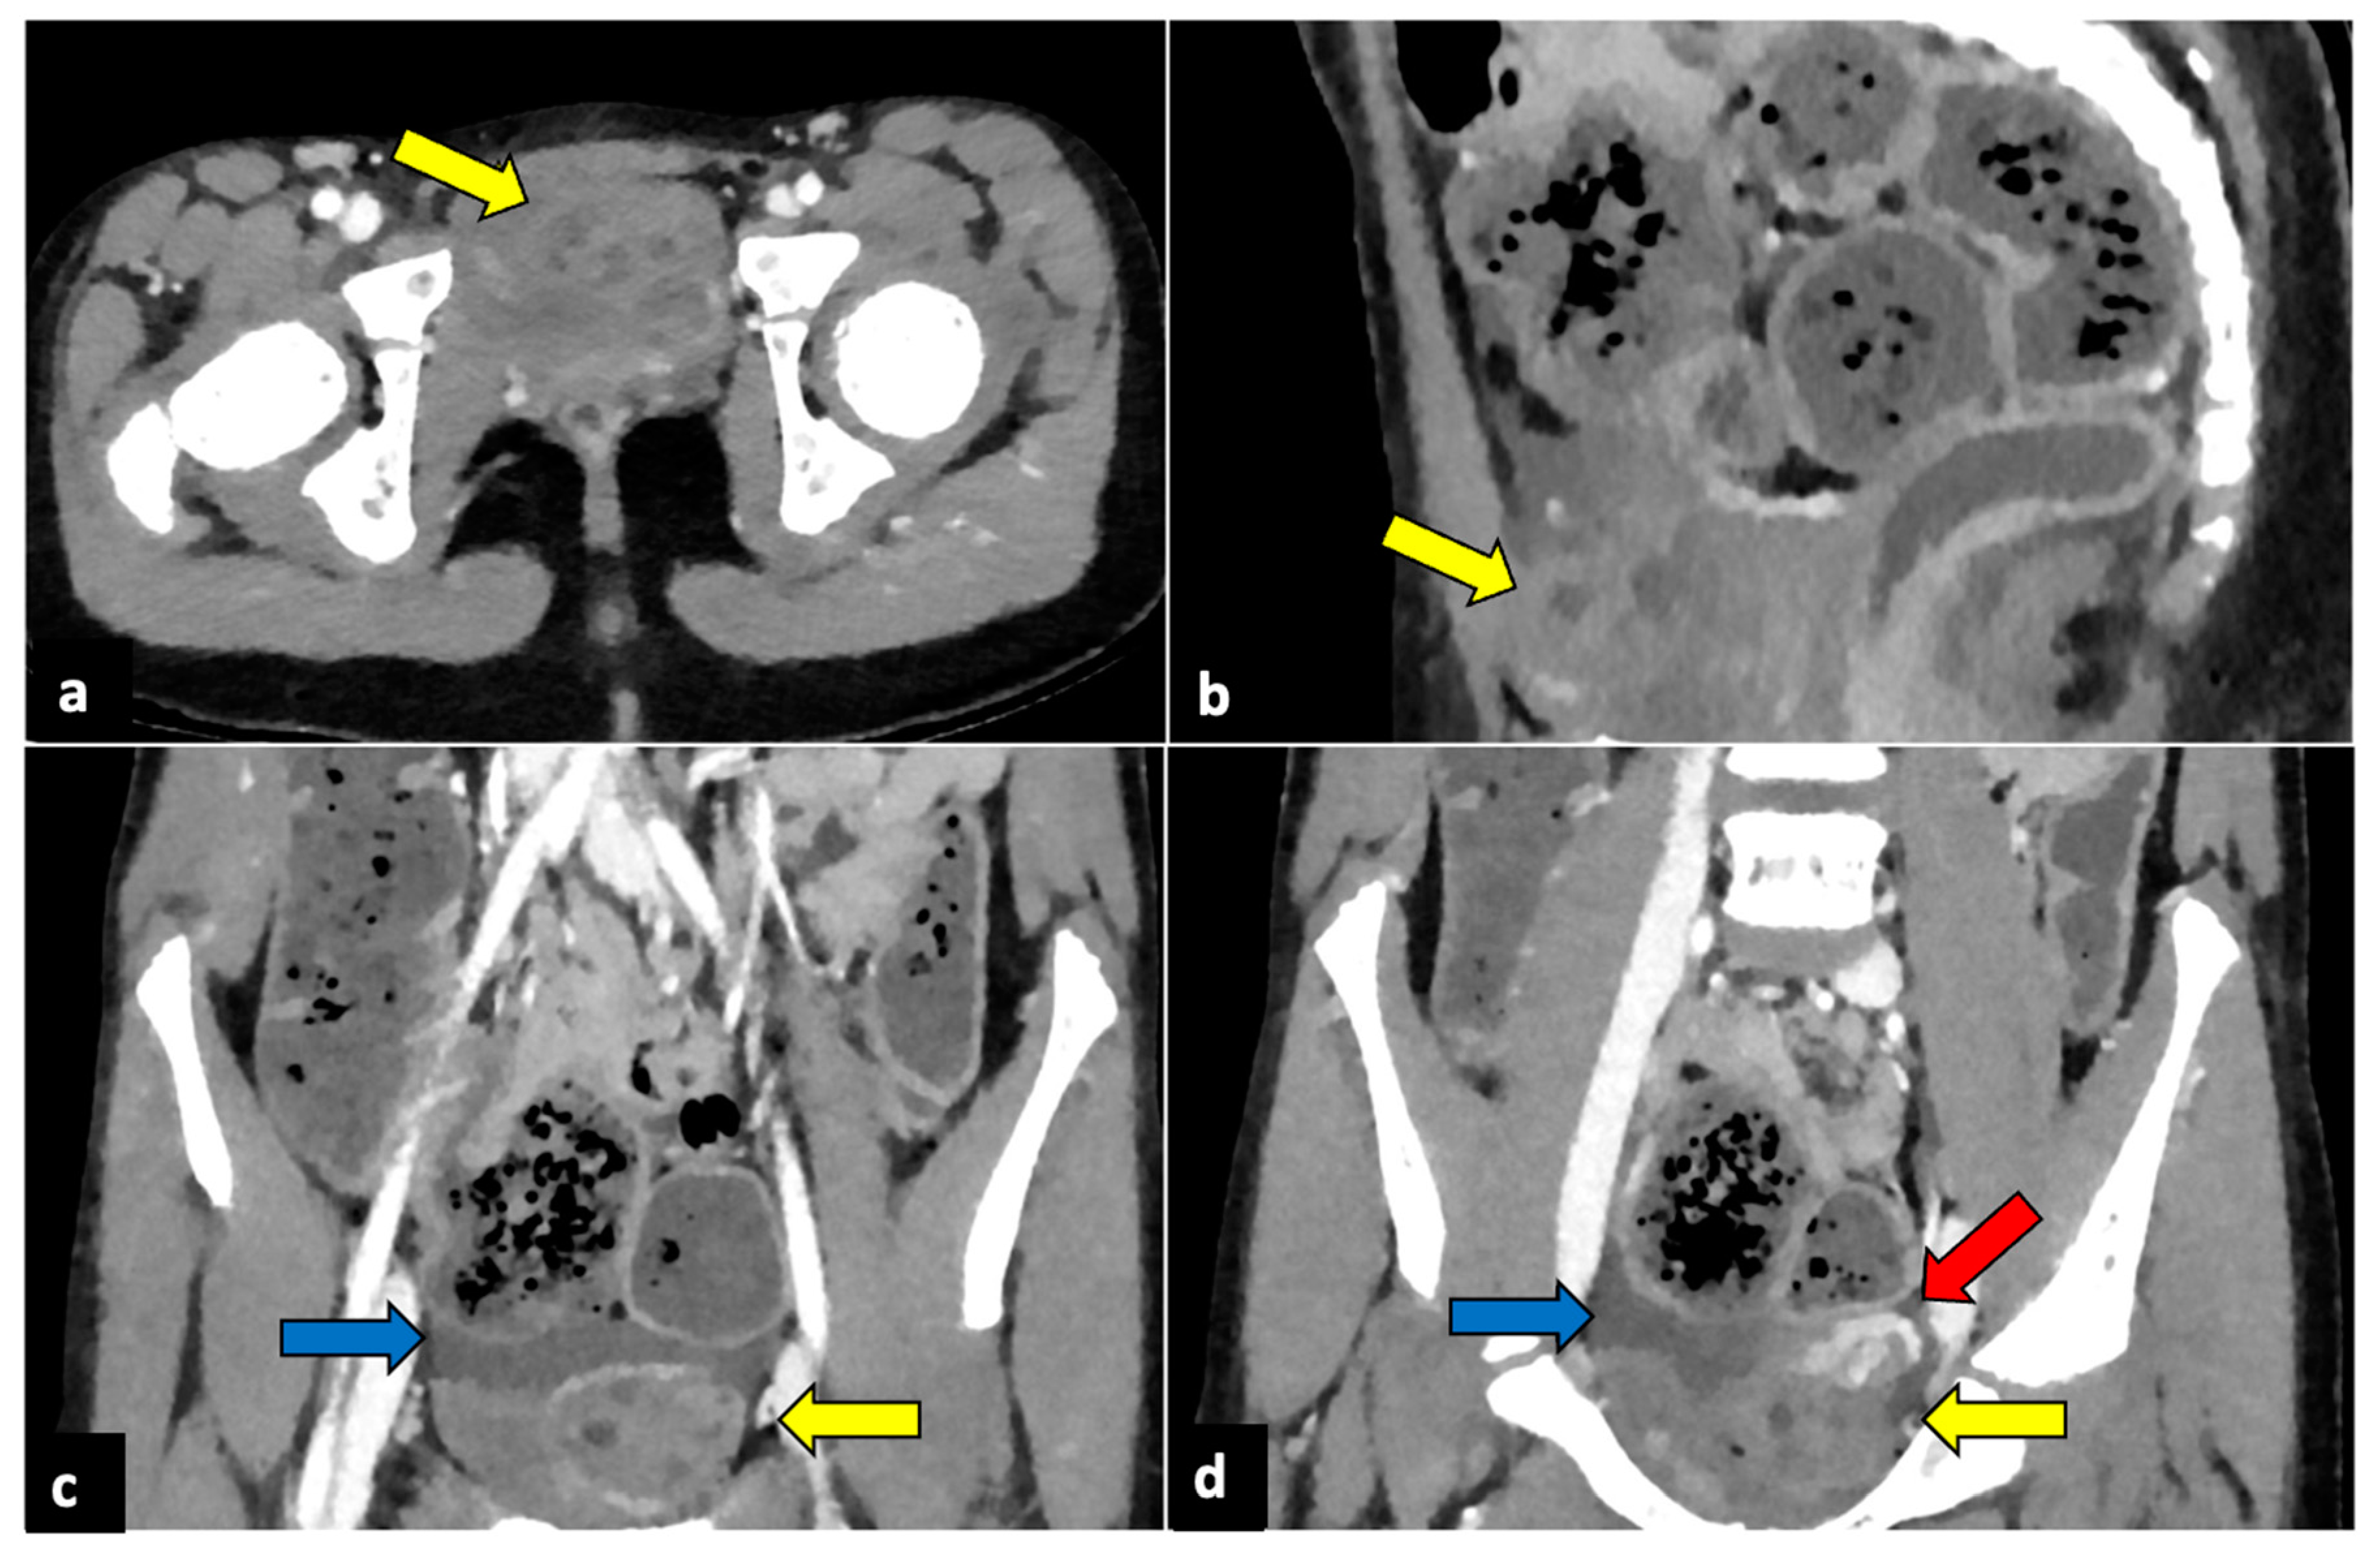

Figure 2.

Left ovarian torsion in a 12-year-old woman with acute lower abdominal pain and vomiting. Axial (a), sagittal (b), and coronal (c,d) contrast-enhanced CT images show enlarged and oedematous left adnexa migrated to the midline and anteriorly to the uterus (yellow arrows), with peripherally displaced ovarian follicles. A small amount of free pelvic fluid (blue arrows) is associated. On the coronal plane, the twisted and oedematous ovarian vascular pedicle (red arrow) can be easily detected.